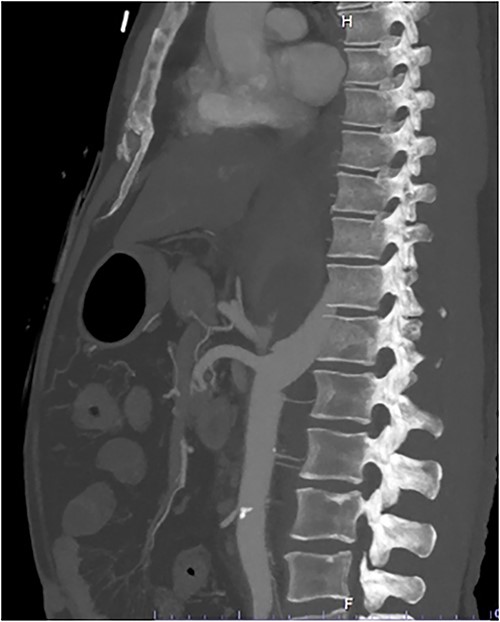

A 54-year-old male presented to our Level 1 Trauma Centre following a high-speed motor vehicle accident with rollover. Although initially haemodynamically stable, significant hypoxia prompted a trauma call activation. On arrival to the Trauma Centre, he had a Glasgow Coma Scale of 8 with an initial heart rate of 70 bpm and systolic blood pressure of 101 mmHg. A brief loss of cardiac output resulted in intubation, bilateral finger thoracostomies and the commencement of massive transfusion. Although his abdominal eFAST was positive, he was fluid responsive and proceeded to imaging. A full computed tomography (CT) trauma series demonstrated CA avulsion (Fig. 1) with contrast extravasation into the retroperitoneum and a large retroperitoneal haematoma measuring 18 cm by 9 cm (Figs 2 and 3). Nil visceral injury was identified and imaging otherwise revealed fractures of the left scapula, right 12th rib and bilateral acetabula and pubic rami.

Coronal CT slice demonstrating coeliac trunk avulsion with active bleeding into a large retroperitoneal haematoma.